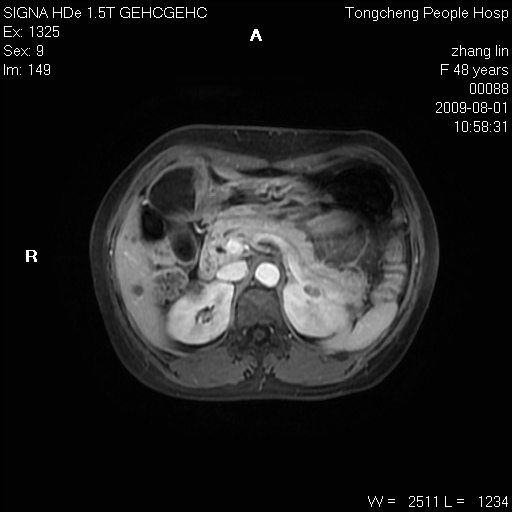

女,48岁。健康体检,彩超发现右肾占位性病变。平素健康。

临床诊断:右肾占位性病变,性质待定(囊肿?肿瘤?)。

上中腹部mr平扫+增强扫描,图像如下:

右肾上极见一类圆形病灶,t1wi呈等信号t2wi呈等高混杂信号,三期增强无强化,边界清---考虑囊肿出血。

同反相位均表现为等信号,病变无强化,考虑含蛋白的囊肿可能,弥散加权相或许有些帮助,

肝囊肿

慢性胆囊炎